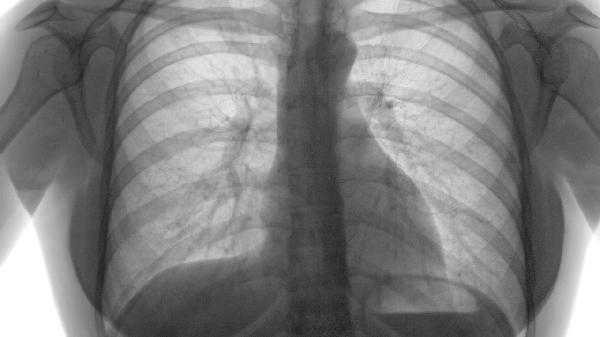

肺气肿的保健护理

肺气肿患者可通过戒烟、呼吸训练、营养支持、预防感染、适度运动等方式进行保健护理。肺气肿是一种慢性阻塞性肺疾病,主要表现为肺泡结构破坏和气体交换障碍,需长期综合管理以延缓病情进展。